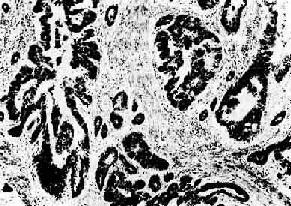

图7-13 腺癌(胃)

癌细胞排列紊乱,多层,形成大小不等、形状不规则的腺样结构,浸润于胃壁组织内